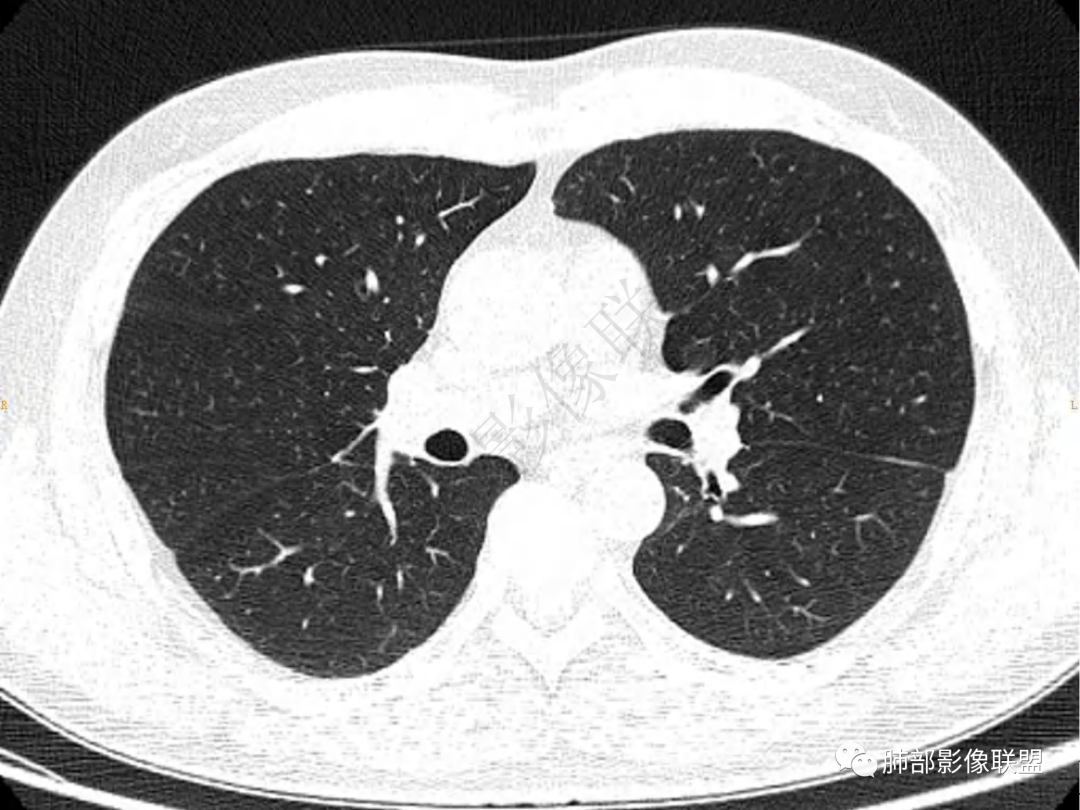

1.中年男性,咳嗽咳痰20余天,间断咯血2周

2.左肺下叶团片影,跨背段及内前基底段,实性部分类椭圆形,密度不甚均匀,可见毛刺及棘状突起,未见典型分叶及胸膜凹陷。病灶上下缘可见相应肺段支气管旁进侧出,管壁轻度增厚,未见狭窄阻塞。

3.周边较大范围磨玻璃影,边界相当模糊,小叶增厚明显。注意叶裂另一侧、左肺舌段亦可见磨玻璃影及增厚的小叶间隔。未见明确卫星病灶。

4.实性部分不均匀环形强化并显示一小范围低密度坏死区或空洞。较之肺窗,整体纵隔窗范围较小,提示病灶并不十分密实。抑或为不同时段图像。

5.双肺门及纵隔未见增大淋巴结。未见胸腔积液。